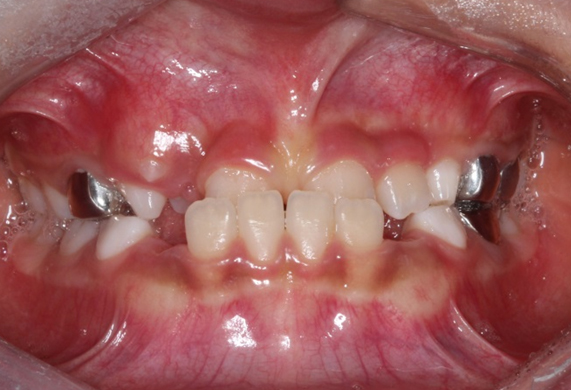

얼굴 골격의 성장에 문제가 있는지를 파악하기 위한 적절한 시기는 초등학교 입학 전인 6-7세경입니다. 이때는 유치에서 영구치로 교환되는 시기로서 부정교합 여부가 결정되는 중요한 시기이므로 이 시기를 잘 관찰하여 부정교합을 예방하는 것 또한 중요합니다. 교정의 정확한 시기는 6개월 간격으로 치과에 정기적으로 내원하여 성장 분석을 받은 후 결정하는 것이 좋습니다.